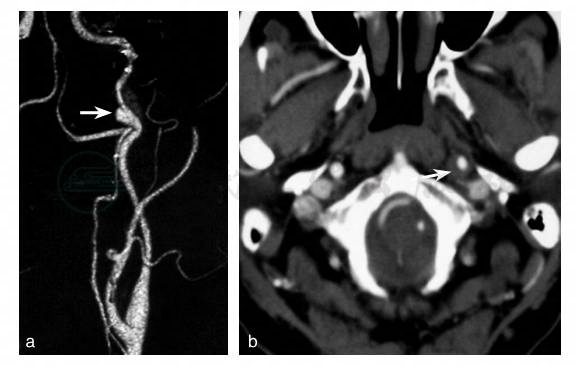

图4 发病后第21天颈部CTA

a:颈部CTA显示左侧颈内动脉颅外段靠近颅底部分血管走行迂曲,局部血管腔呈囊状扩张(白箭头),囊状扩张远侧局部管腔狭窄;b:CTA原始图像可见狭窄部位局部颈动脉外径增大,造影剂充盈之血管腔为月牙形等密度影所包绕(白箭头)